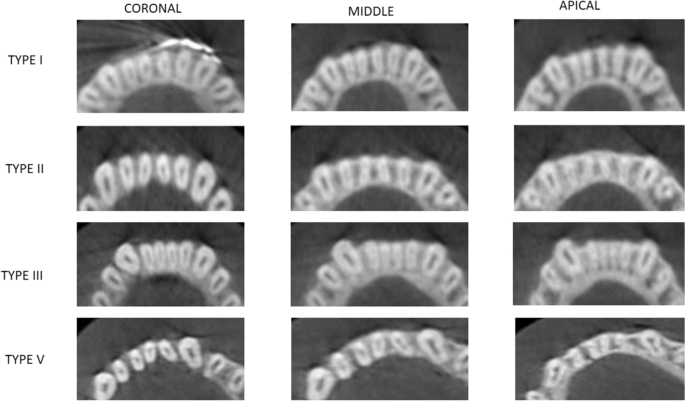

The different levels to detect canal morphology was based on the study by Kurumboor K. In this study, the average root length of mandibular central incisor was 12.9 mm and lateral incisor was 12.83 mm. Based on this findings, each section was studied at three levels i.e. 3 mm from apex to study apical third, 6 mm from apex for middle third and 9 mm from apex for coronal third, all three studied in axial section of CBCT scans37.

The root canal morphology of the mandibular central and lateral incisors was assessed in sagittal sections at three different levels: 3 mm from the radiographic apex to assess the morphology in the apical third; 6 mm from the apex to assess the morphology of the canals in the middle third of the root; and 9 mm from the apex to assess the morphology of the canals in the coronal third of the root.

The canal configuration and the numbers of the roots and canals of the central and lateral incisors were classified according to Vertucci’s classification16.

Overall, 66.75% (534 of 800) of the mandibular central incisors showed a simple (Vertucci Type I) root canal morphology. Of the 800 central incisors evaluated, 68% (272 of 400) on the right and 65.5% (262 of 400) on the left side showed a simple canal morphology (Table 5) (p > 0.01) (Fig. 6).

Approximately 33.25% (266 of 800) of the mandibular central incisors showed a complicated root canal morphology (Type III, V, or II). Complicated root canal morphology including Vertucci’s Type II, III, IV, and V was found in 32% (128 of 400) of MCIs on the right side and 34.5% (138 of 400) of the left side. Vertucci Type III (28.3% on the right side and 31% on the left side) canal configuration was the second most common root canal morphology for the mandibular central incisors, followed by Type V and II (p > 0.01) (Table 5).

Mandibular lateral incisors

Overall, 58.62% (469 of 800) of the mandibular lateral incisors showed a simple (Vertucci Type I) root canal morphology. Of the 800lateral incisors evaluated, 58.3% (233 of 400) on the right and 59% (236 of 400) on the left side showed a simple canal morphology (p > 0.01) (Table 5) (Fig. 6).

Approximately 41.37% (331of 800) of the mandibular lateral incisors showed a complicated root canal morphology (Type III, V, or II). Complicated root canal morphology including Vertucci’s Type II, III, IV, and V was found in 41.75% (167 of 400) of MCIs on the right side and 41% (164 of 400) of the left side. Vertucci Type III (34.8% on the right side and 35.8% on the left side) canal configuration was the second most common root canal morphology for the mandibular lateral incisors, followed by Type V and II (p > 0.01) (Table 5).

In the current study, the mandibular central and lateral incisors on both the right and left sides showed predominance for Vertucci Type I configuration. Vertucci Type I canal configuration showed the highest occurrence (58–70%), followed by Type III (26–35%). These findings corroborate those of the studies conducted by Kaffe et al.18, Verma et al.19, Rahimi et al.20, Saati et al.21, Han et al.55, and Liu et al.36. In an Indian subpopulation, Verma et al. found that the most common canal configuration was Vertucci’s Type I, which was then followed by Type III (15.25%), II (12.12%), V (3.12%), and Type IV (2.37%). Compared with mandibular central incisor, mandibular lateral incisors showed a higher prevalence of having more than one root canal. This finding corroborates those of previous studies that have shown that when compared to other mandibular anterior teeth, the lateral incisors have a greater incidence of multiple root canals. In our study, complicated root canal morphology was found more commonly in the age group more than 44 years which was contrary to that found in the Cantonese population. There was no statistically significant difference between root canal anatomy and side, age or gender (p > 0.05).